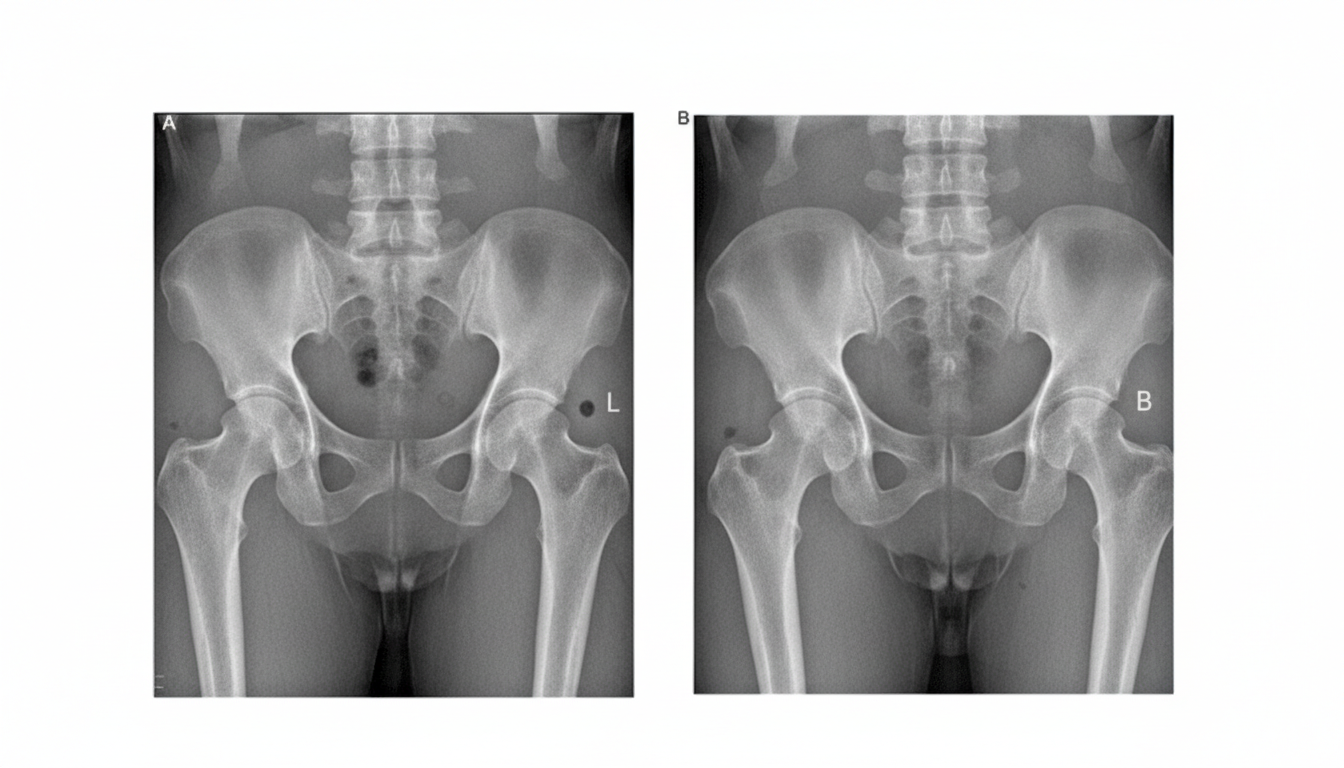

A 63-year-old woman presents to her physician with hip pain. She has had pain in both hips for almost 5 years, and it has progressed over time. She notes that it gets worse as the day goes on, making it difficult for her to walk her small dog in the evening. She has a little morning stiffness which subsides quickly after she starts to walk. In the last week, her pain became worse. The past medical history includes hypertension, hyperlipidemia, and mild hypothyroidism. She takes captopril, atorvastatin, and levothyroxine. She has also been taking acetaminophen almost every day with a dose increase up to 4,000 mg, but there is no significant decrease in pain. Both of her parents died in their 80's. The blood pressure is 135/85 mm Hg, heart rate is 74/min, respiratory rate is 12/min, and the temperature is 37.0°C (98.6°F). The BMI is 35 kg/m2. On physical examination, the leg strength is normal bilaterally. The neurological exam of both upper and lower extremities is normal. Her gait is difficult to assess due to pain. A radiograph of her left hip joint is shown in the image below. Which of the following is the most appropriate treatment for the patient’s condition?

Explanation: ***Switching acetaminophen to meloxicam*** - The patient presents with classic symptoms of **osteoarthritis (OA)**, including progressive hip pain, worsening with activity, and minimal morning stiffness, along with radiographic evidence of severe OA (joint space narrowing, osteophytes, subchondral sclerosis, and cysts) in the left hip. As **acetaminophen (paracetamol)** at 4000 mg/day is no longer effective, a **non-steroidal anti-inflammatory drug (NSAID)** like meloxicam is the next appropriate step for pain management in OA, especially given her relatively healthy status for NSAID use. - **Meloxicam** is a selective COX-2 inhibitor, which may have a slightly lower risk of gastrointestinal side effects compared to non-selective NSAIDs, making it a reasonable choice if tolerated. *Addition of intra-articular hyaluronic acid injections* - **Intra-articular hyaluronic acid injections** (viscosupplementation) are sometimes used in knee osteoarthritis, but their effectiveness in **hip osteoarthritis** is less well-established and generally considered for patients who have failed oral therapies and are not yet candidates for surgery. - Given the severe radiographic findings, this patient is likely beyond the stage where these injections would provide significant long-term relief, and oral NSAIDs should be tried first if acetaminophen failed. *Switching acetaminophen to oral methylprednisolone* - **Oral corticosteroids** like methylprednisolone are generally **not recommended** for the long-term management of osteoarthritis due to significant systemic side effects such as osteoporosis, hyperglycemia, and immunosuppression. - While they can provide temporary pain relief due to their anti-inflammatory properties, their chronic use for OA is discouraged. *Increasing the dose of acetaminophen to 6000 mg per day* - The **maximum recommended daily dose of acetaminophen** for adults is generally 3000-4000 mg (3-4 grams) to avoid **hepatotoxicity**. - Increasing the dose to 6000 mg (6 grams) per day would significantly increase the risk of **severe liver damage** and is therefore contraindicated. *Addition of glucosamine supplementation* - **Glucosamine supplementation** has shown **inconsistent efficacy** in clinical trials for osteoarthritis and is generally not recommended as a primary treatment. - There is little evidence to support its ability to slow disease progression or significantly reduce pain in moderate to severe osteoarthritis, particularly when compared to proven pain management strategies like NSAIDs.